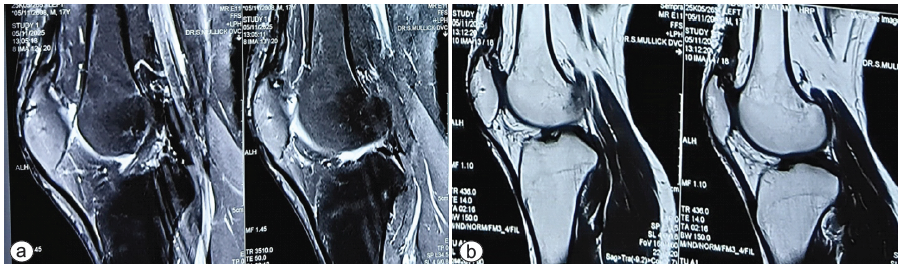

We did an MRI recently, to look for any abnormality, but the MRI showed that the quadriceps was intact, and no sign of AVN was noted over the upper pole of the patella (Fig. 6a and b).

Figure 6: (a and b) Recent magnetic resonance imaging showing the intact quadriceps.